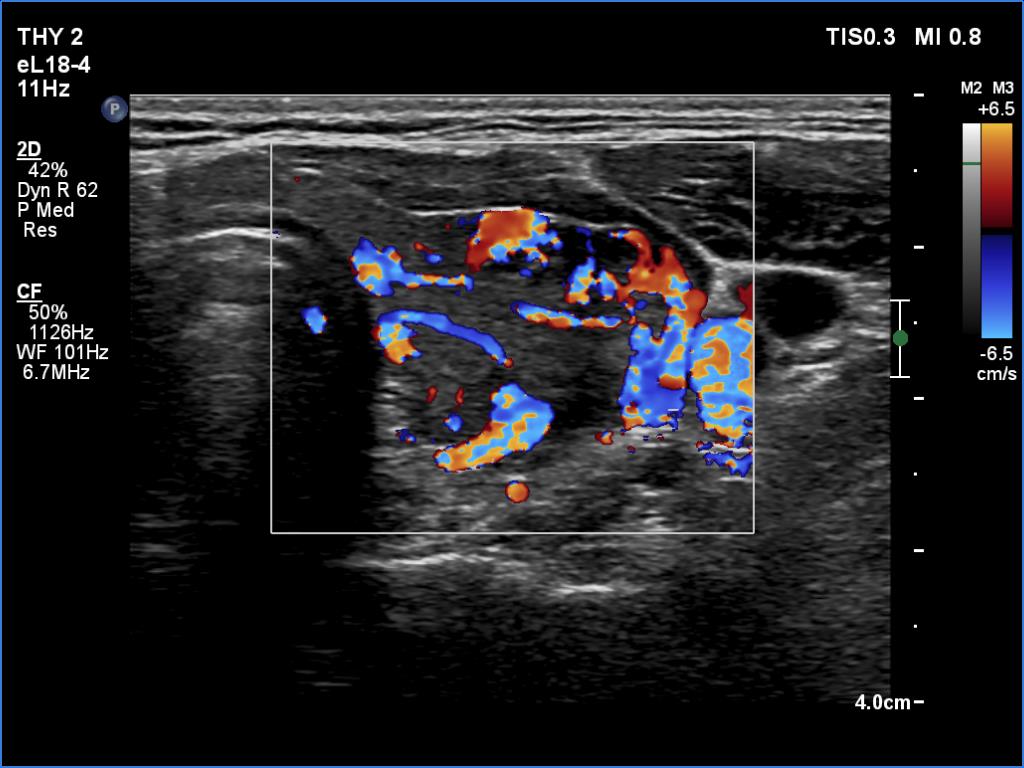

Follow-up examination 9 months after the first visit (ultrasonographic picture 7)

Left lobe, transverse scan, color Doppler mode. The vascularity is still increased in this lobe, however, to a much lesser extent.